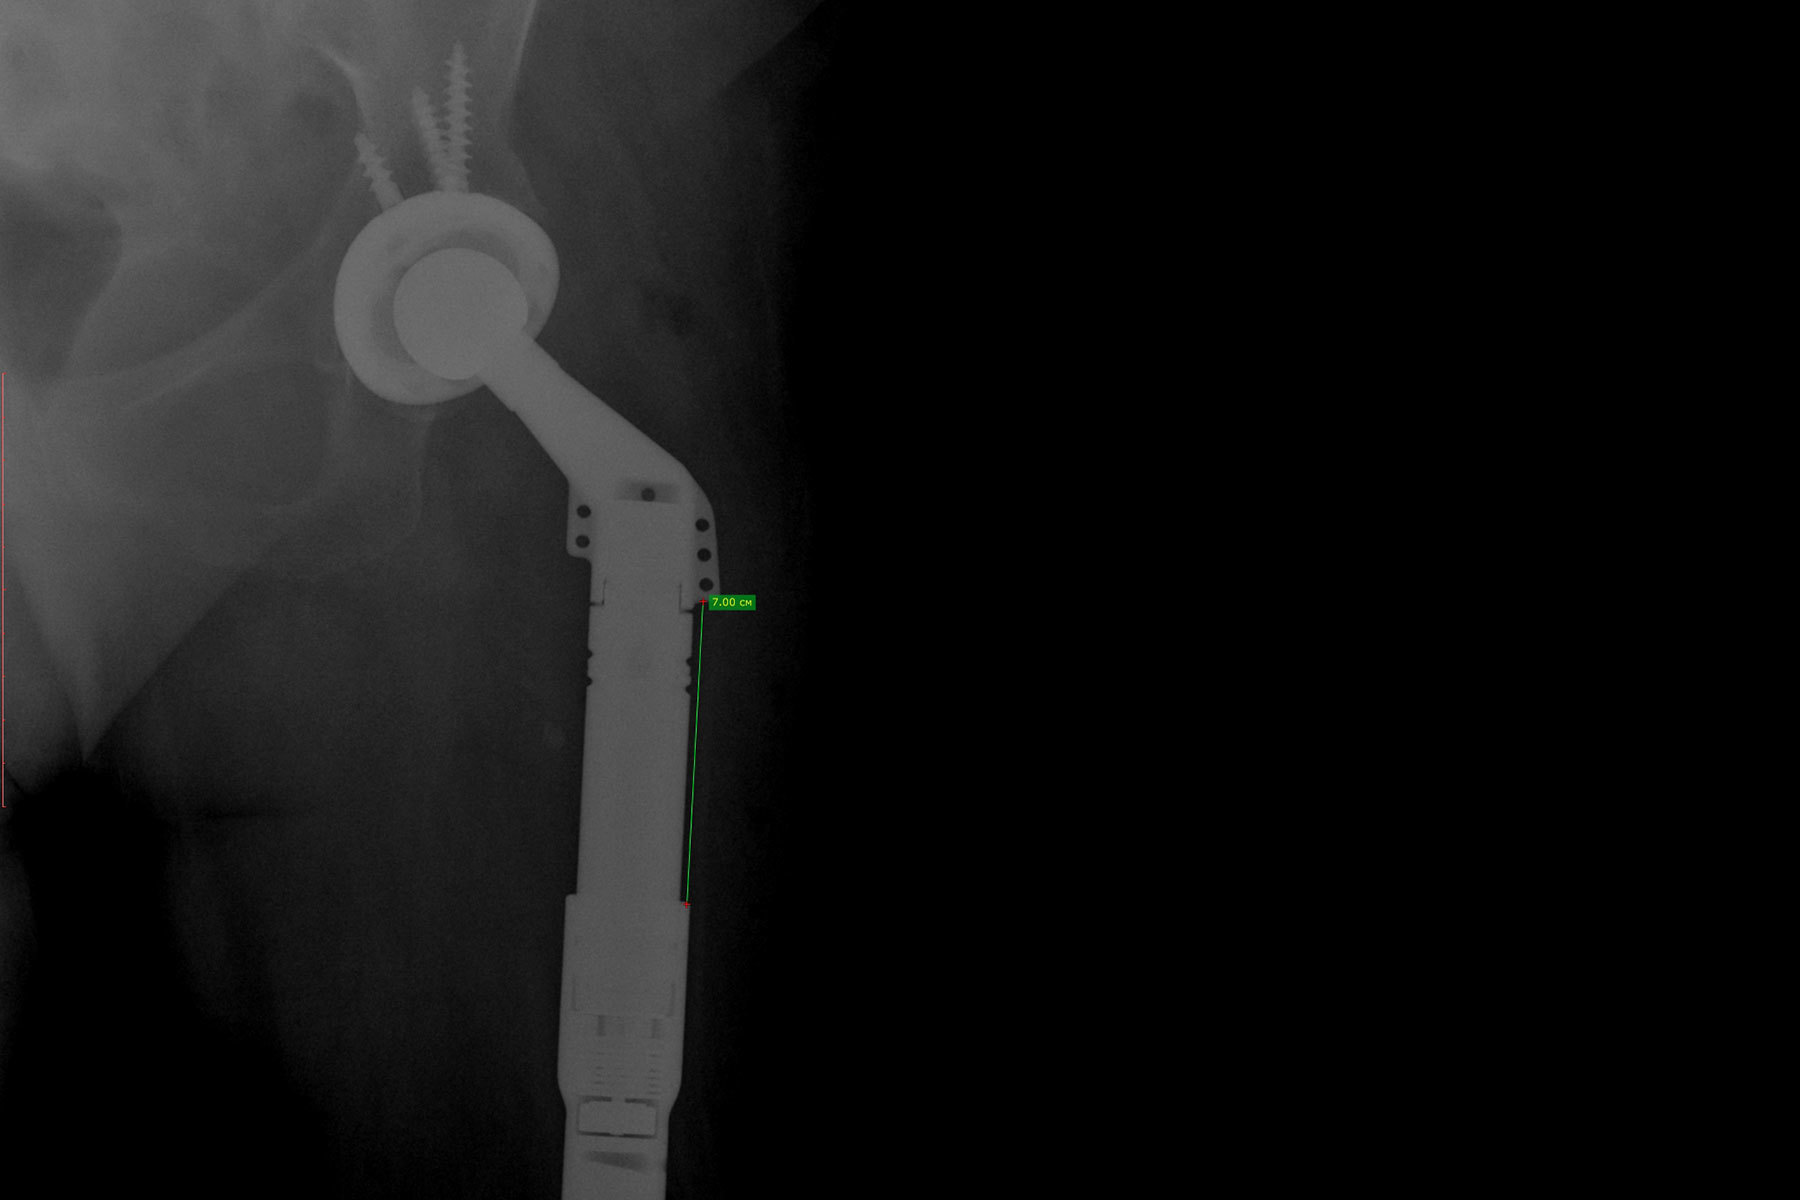

Более 20 раздвижных эндопротезов, созданных в Самарском государственном медицинском университете Минздрава России, установлено в медучреждениях страны. Эндопротез позволяет изменить его длину без повторной операции и «растет» вместе с маленьким пациентом: входящий в конструкцию магнитный редуктор раскручивается внешним магнитным полем и раздвигает штифт внутри протеза. Благодаря этому происходит телескопическое увеличение длины компонента эндопротеза. Раньше такие имплантаты изготавливали только зарубежные компании.

Раздвижные эндопротезы применяются в детской реконструктивной ортопедии и онкологии. Они изготавливаются по индивидуальным параметрам пациента. Размеры протеза и возможности его удлинения зависят от размера костей. Самый маленький протез установили пятилетнему ребенку. Максимально был изготовлен и установлен протез, раздвигающийся на 11 см.